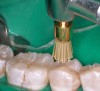

Figure 9  Gross finishing and marginating of the occlusal surface of a posterior composite resin restoration with an 8-bladed finishing bur (Brasseler USA).

Figure 9